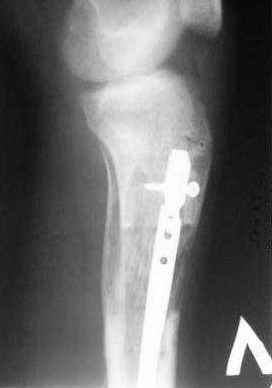

5, 6 - через 2,5 мес после травмы выполнен закрытый остеосинтез блокируемым штифтом.

7, 8, 9, 10, 11 - через 8 мес после травмы перелом сросся.

Пациент ходит без дополнительной опоры, не хромает (видеоролик выложил сюда